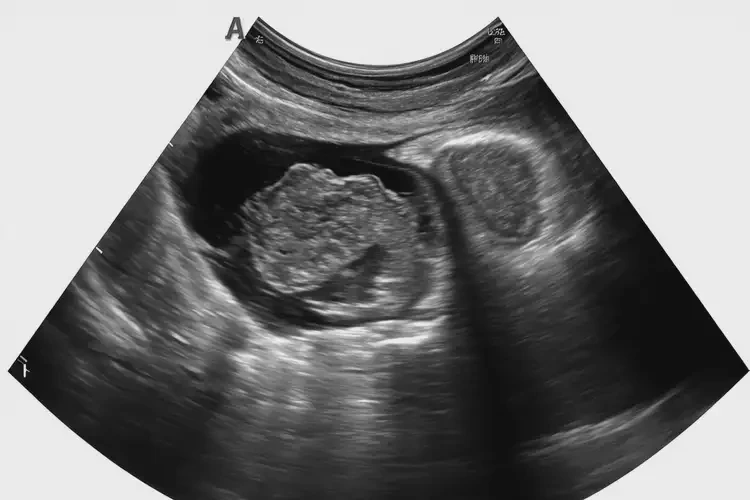

懷孕第17周胎心率85寶寶還能要嗎(圖2)

2. 胎兒超聲檢查

• 胎兒超聲檢查可以評(píng)估胎兒的發(fā)育情況、心臟功能以及是否存在其他結(jié)構(gòu)異常。

• 超聲檢查還可以觀察胎盤(pán)和臍帶的情況,以排除缺氧的可能性。